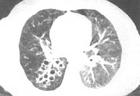

支氣管擴張症可為單側或雙側,大多數位於下葉,但也常發生於右肺中葉和左上肺舌葉.傳統上根據病理和X線表現將其分為圓柱狀,曲張狀或囊狀.然而,這種區分臨床價值不大.最近,病理與高解析度及螺鏇CT特徵的相關已使這種分類趨於棄用.

述症狀和體徵提示支氣管擴張症,胸部X線檢查示肺紋理增深(由於外周支氣管纖維化和管內分泌物瀦留),聚攏(由於肺不張),"軌道征",由於外周支氣管炎症和纖維化),蜂窩狀區,伴有或不伴有液平面的囊性區.偶爾X線也可正常.胸部高解析度CT(HRCT)(1~2mm層厚)已基本上取代支氣管造影.採用10mm校正,擴張的小支氣管可能不被顯影,但HRCT良好的解析度所提供的結果可與支氣管造影媲美,甚至優於後者.廣泛採用HRCT顯示支氣管擴張症要比依靠臨床和胸片作出的診斷更為常見.